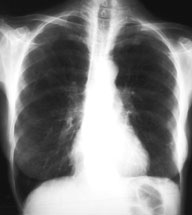

Eine 70-jährige Patientin meldet sich bei Ihnen in der Praxis mit Verschlechterung des Allgemeinzustandes seit 4-5 Wochen und Fieber bis maximal 38.5 Grad.

Des weitern klagt sie über einen trockenen Husten. Ausser einer arteriellen Hypertonie besteht als Vorerkrankung eine leichte COPD. Da Sie ausser dem Husten keinen klinischen Fokus für einen Infekt finden, entschliessen Sie sich für ein Thorax-Bild. Optimalerweise haben Sie sogar noch ein pa-Thorax von vor 2 Jahren zum Vergleich:

Thorax pa vor 2 Jahren

Bild vergrössern

Welche Differentialdiagnosen kommen in Frage (mehrere richtige Antworten möglich)?